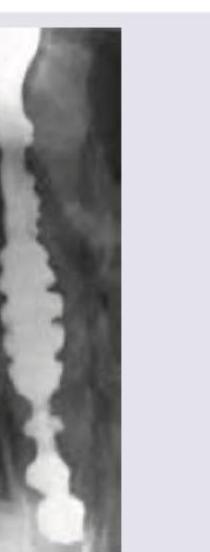

The neck X-ray of a patient shows:

Explanation: ***Fish vertebra*** - The image indicates **biconcave vertebral bodies** with a central depression, mimicking the appearance of a **fish vertebra**. This shape results from bone softening conditions, leading to compression of the vertebral body by the turgid intervertebral discs. - This finding is classically associated with **osteoporosis** or **osteomalacia**, where the bone mineral density is reduced making the vertebrae more susceptible to this type of deformation. *Hemivertebra* - A hemivertebra is a **congenital anomaly** where only half of a vertebral body forms, causing a wedge-shaped vertebra and often leading to **scoliosis**. - The image does not show a malformed, wedge-shaped vertebral body; instead, it shows a **biconcave deformity** of a fully formed vertebra. *Rugger jersey spine* - Rugger jersey spine refers to the appearance of alternating lucent and sclerotic bands on the superior and inferior endplates of vertebral bodies, resembling the stripes on a rugby jersey. - This finding is characteristic of **renal osteodystrophy** due to secondary hyperparathyroidism, which is not depicted in the given image. *Block vertebra* - A block vertebra is a **congenital or acquired fusion** of two or more adjacent vertebral bodies, resulting in a single, enlarged vertebral segment with rudimentary or absent intervertebral discs. - The image clearly shows distinct vertebral bodies with intervening discs, albeit distorted, and no evidence of fusion.

Explanation: ***Steeple sign*** - The image shows a **narrowing of the subglottic trachea**, which resembles a "steeple" or a church spire on a frontal neck X-ray. - This sign is highly suggestive of **croup** (laryngotracheobronchitis), caused by inflammation and edema of the subglottic region. *Zenker's diverticulum* - This is an **outpouching of the posterior pharyngeal wall** through Killian's triangle, typically seen as a fluid or air-filled sac posterior to the esophagus. - It would appear inferior to the larynx and esophagus, not as a tracheal narrowing within the airway. *Laryngocele* - A laryngocele is an **abnormal air-filled dilation of the laryngeal saccule**, usually appearing as a radiolucent mass in the neck, often extending into the soft tissues. - It would be located more superiorly and laterally to the trachea and does not present as a classic subglottic narrowing. *Thumb sign* - The **"thumb sign"** refers to the appearance of an **enlarged, edematous epiglottis** on a lateral neck X-ray, resembling a thumb. - This sign is characteristic of **epiglottitis**, a different condition affecting the supraglottic region, not the subglottic trachea.